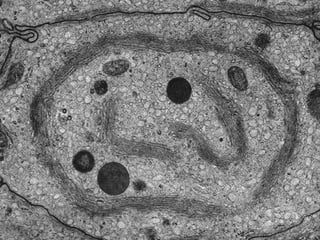

Este documento presenta imágenes microscópicas de diferentes tipos de tejidos y estructuras celulares teñidas con varios métodos histológicos. Incluye fotografías que muestran fibras de colágeno, elásticas y reticulares en diversos órganos, así como membranas basales y células especializadas de órganos como riñones, glándulas mamarias y próstata. El propósito es demostrar la aplicación de técnicas histológicas para visualizar componentes celulares y tej